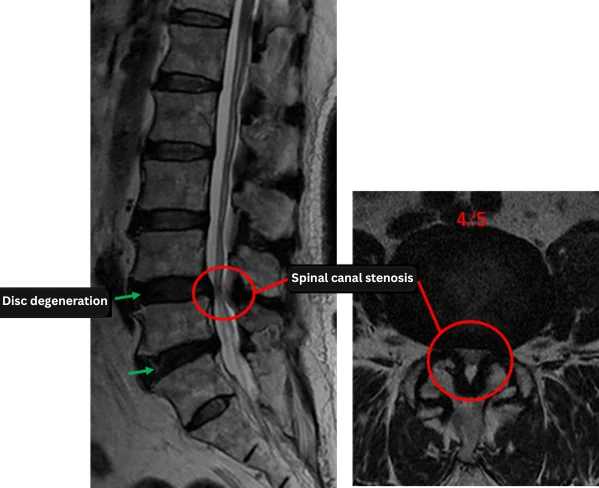

Imaging and findings

L1/2: Normal condition

L2/3: Normal condition

L3/4: Normal condition

L4/5: Disc degeneration, disc bulging, ligamentum flavum hypertrophy, spinal canal stenosis

L5/S: Disc degeneration, disc bulging

The above findings were also observed on the imaging.

At L4/5 and L5/S, disc degeneration, disc bulging, ligamentum flavum hypertrophy, and spinal canal stenosis were observed and were considered highly likely to be the primary causes of the patient’s symptoms.